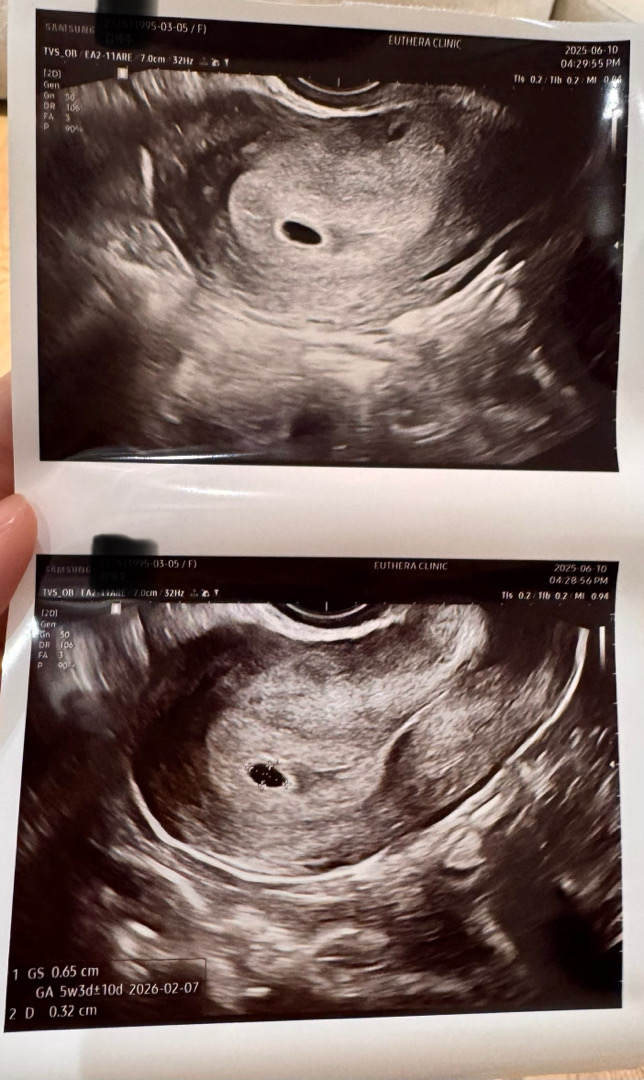

어제 초음파 보구왔어요!!

애기집이라니 너무 귀여워용 ㅠㅠ 애기집은 있는데 정확한 주수랑 예정일 나오려면 다음주되야한대요ㅠㅠ 그래도 대략 2월이라구 하네요~~

제가 그런걸 잘 계산못해요ㅠㅠ 생리 시작일이 4/29이었구 처음 임테기 두줄 뜬날이 6/4이었어요! 그땐 피검사만 했었구 어제 갔더니 아기집 보였네요 ㅎㅎ